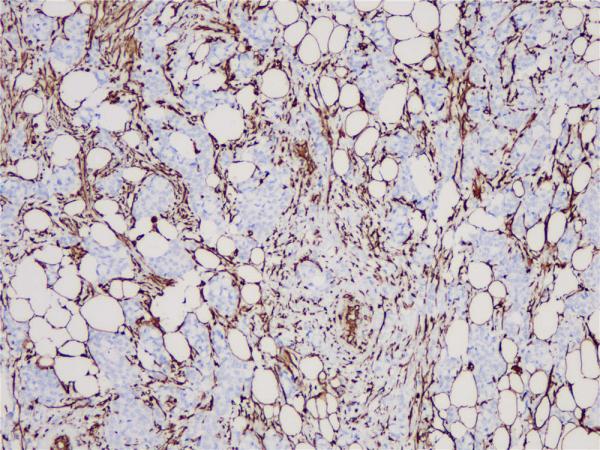

Vimentin

BP6010